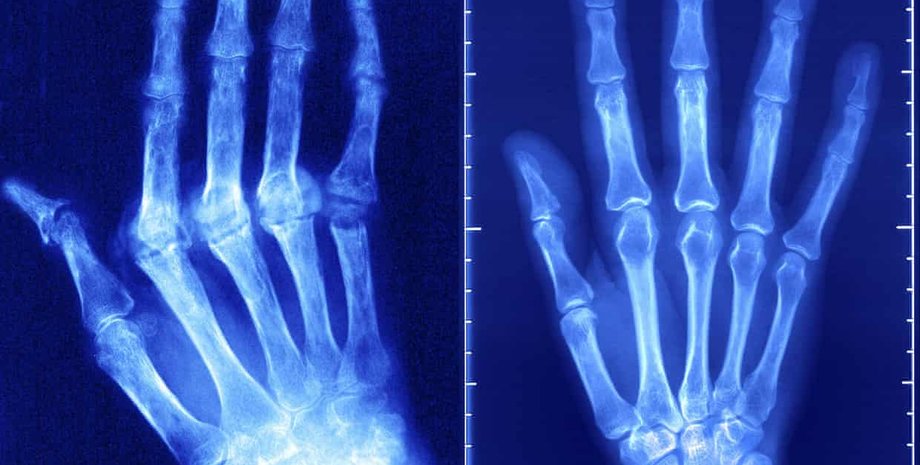

Число случаев аутоиммунных заболеваний увеличивается на 3-9% в год | Фото: The Guardian

Аутоиммунные заболевания, число которых растет на 3-9% в год, начали появляться в тех странах, где их никогда не было.

Аутоиммунные заболевания варьируются от диабета 1 типа до ревматоидного артрита, воспалительных заболеваний кишечника и рассеянного склероза.